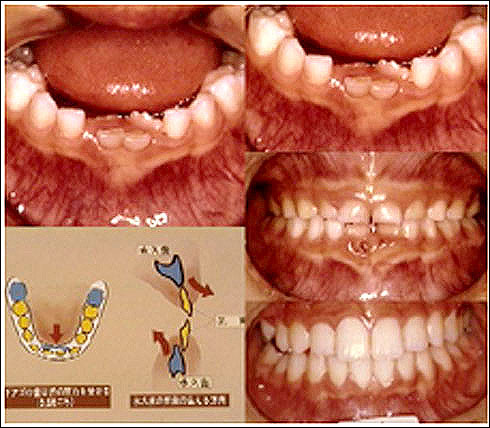

舌小帯と開咬

舌の運動機能障害

症例

永久歯が後ろから!?